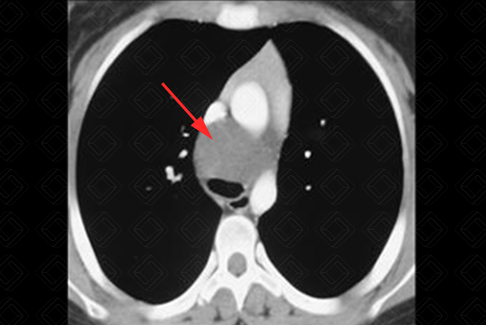

Texto alternativo para a imagem Figura 1. Créditos: Dra. Elazir Mota - Rio de Janeiro/RJ

Descrição da figura 1: Cisto de duplicação (seta vermelha).

• O mediastino médio contém as seguintes estruturas: linfonodos, traqueia, esôfago, veia ázigo, veia cava, coração e arco aórtico. As principais lesões aqui são os cistos de duplicação intestinal ou linfonodomegalias (f igura 1);